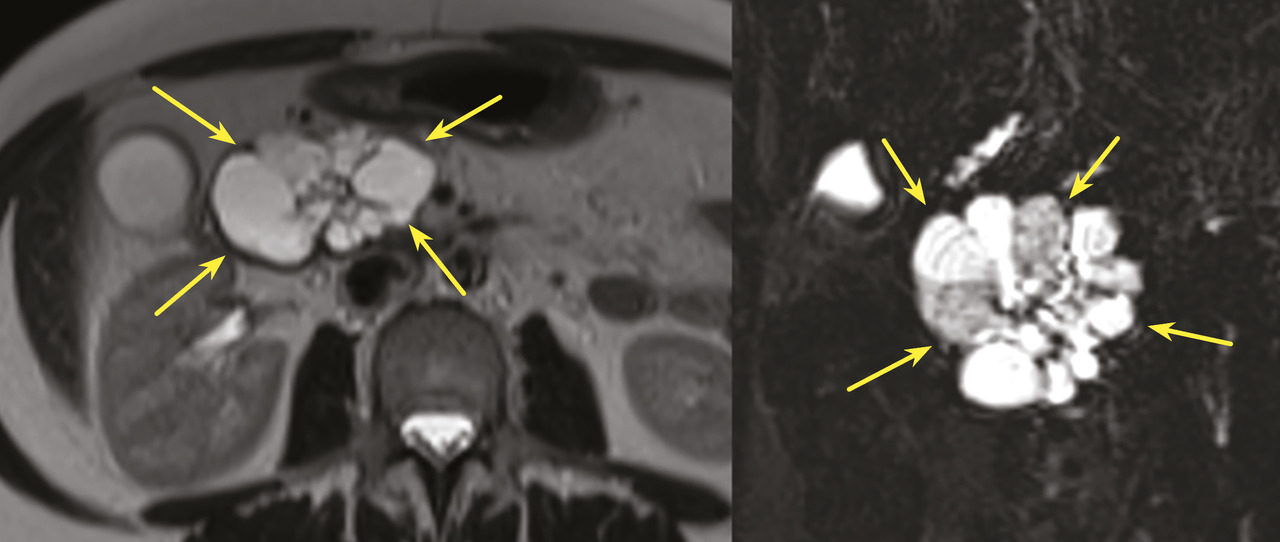

Tumeur kystique mucineuse

Les tumeurs kystiques mucineuses (TKM) sont des lésions précancéreuses bordées par un revêtement épithélial, sécrétant de la mucine. Il est caractéristique de trouver un stroma de type ovarien, positif en immunohistochimie à la progestérone. Le sex-ratio est fortement en faveur des femmes  : (20 femmes pour 1 homme). La découverte est principalement fortuite ou plus rarement sur pancréatite aiguë. Il s’agit d’une lésion unique, macrokystique, sans communication avec les canaux pancréatiques. Elle se situe quasi exclusivement au niveau de la face postérieure du corps et de la queue du pancréas (fig. 3). La lésion est uni- ou multiloculaire, limitée, hypodense, avec rehaussement de la paroi. Il existe de possibles nodules muraux, calcifications périphériques ou cloisons internes.

Le taux de risque d’évolution vers un cancer est inconnu. Les critères comme une taille supérieure à 7 cm, une épaisseur des septas et de la paroi supérieure à 3 mm, un nombre de kystes supérieur à quatre, la présence de nodules, un contenu liquidien hyperintense en séquences IRM T1, une compression ou infiltration périlésionnelle sont associés à des critères de dégénérescence en cystadénocarcinome.11

Dans les recommandations européennes, les experts proposent (à l’instar des TIPMP) une surveillance si la taille de la lésion est inférieure à 40 mm, en cas d’absence de nodules et si le patient est asymptomatique. Pour les lésions de 30 à 40 mm, il est recommandé de prendre en compte l’âge et les comorbidités. Les modalités de surveillance sont la réalisation d’une IRM ou d’une écho-endoscopie tous les six mois pendant un an puis tous les ans. En cas de résection, celle-ci doit être la plus limitée possible, en privilégiant la chirurgie d’épargne de type énucléation ou pancréatectomie médiane. Le risque de récidive postopératoire est nul, il n’est pas recommandé de suivi spécifique si la résection était complète.